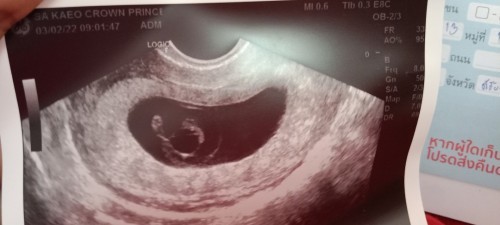

หมอบอกน้องได้ 6 สัปดาห์แล้ว แต่น้องยังไม่มีหัวใจ มันจะเป็นรัยไหมคะ กลัวจัง